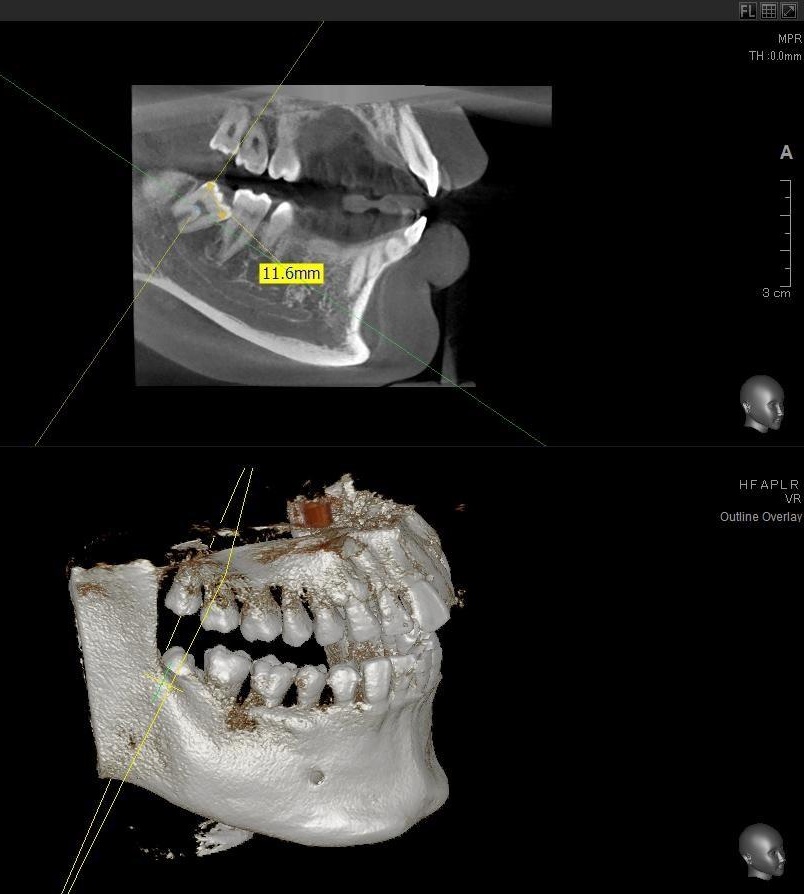

さらに、下顎の親知らずは下歯槽神経に非常に近いところに生えている場合もあるため、CTも撮影し詳しい解析を行います。

親知らずが生えている位置が、神経に近い、あるいは神経に当たっている場合は、大きな病院に紹介する場合もあります。

親知らずの根っこは下歯槽神経から近い距離にありますが、抜歯は可能との診断でした。